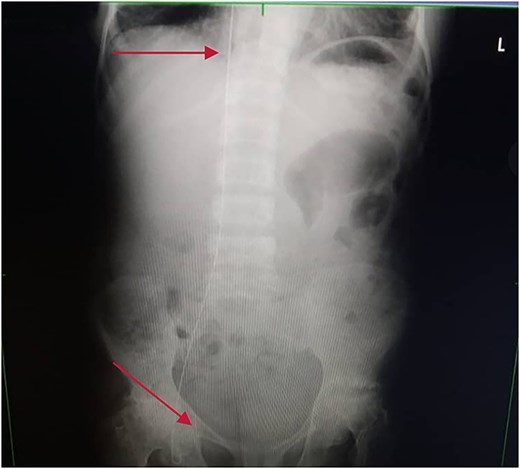

Chest and abdominal X-rays revealed the guide wire extending from the right subclavian vein through the superior vena cava (SVC), right atrium, and inferior vena cava (IVC) to the proximal right femoral vein (Figs 5 and 6).

Plain abdominal X-ray extending from the IVC through the right iliac vein to the right femoral vein.